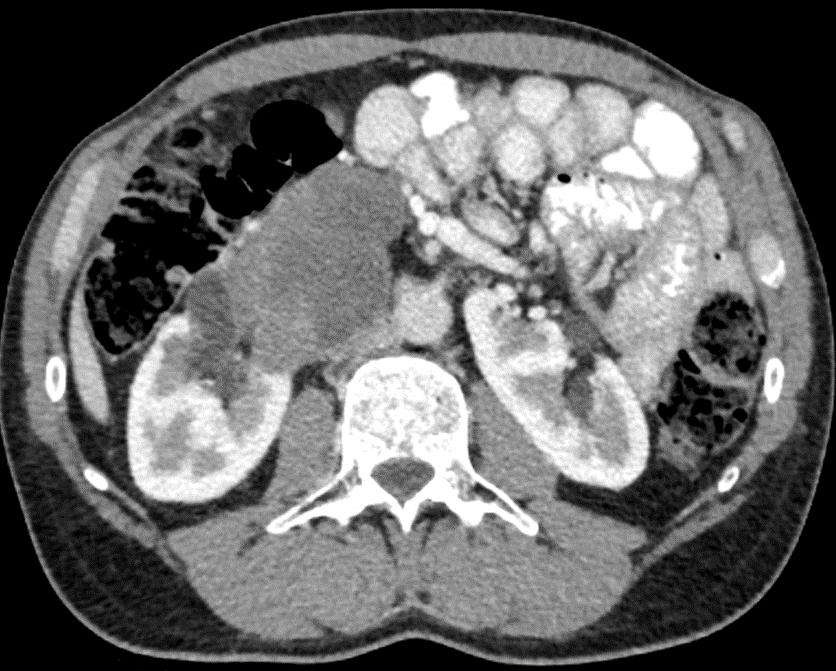

Obr. 1. Perioperační CT snímek během MWA.

Fig. 1. Perioperative CT scan during microwave ablation.

Výkon byl prováděn mikrovlnným systémem Solero Microwave Tissue Ablation System (AngioDynamics, Inc., USA). Během ablačních výkonů byla používána frekvence 2,45 GHz a výkon v rozsahu 100–140 W. Jako aplikátor byla používána nerezová ocelová jehla s keramickým hrotem o průměru 15 G a délce 14, 19 nebo 29 cm. Jedna ablační sekvence po zavedení jehly do tumoru trvá 4–6 min podle velikosti nádoru, v průběhu jednoho výkonu jsou standardně prováděny 1–2 ablační sekvence. Maximální velikost ablační zóny udávaná výrobcem je 54 × 39 mm na jednu sekvenci. Po skončení ablace tumoru se během vytahování jehly provádí ablace-koagulace punkčního kanálu (track ablace). Výkon je prováděn v analgosedaci za přítomnosti anesteziologa, pacienti snášejí výkon dobře. Celková doba výkonu vč. polohování pacienta a přípravy CT pracoviště je 60–90 min (obr. 1).